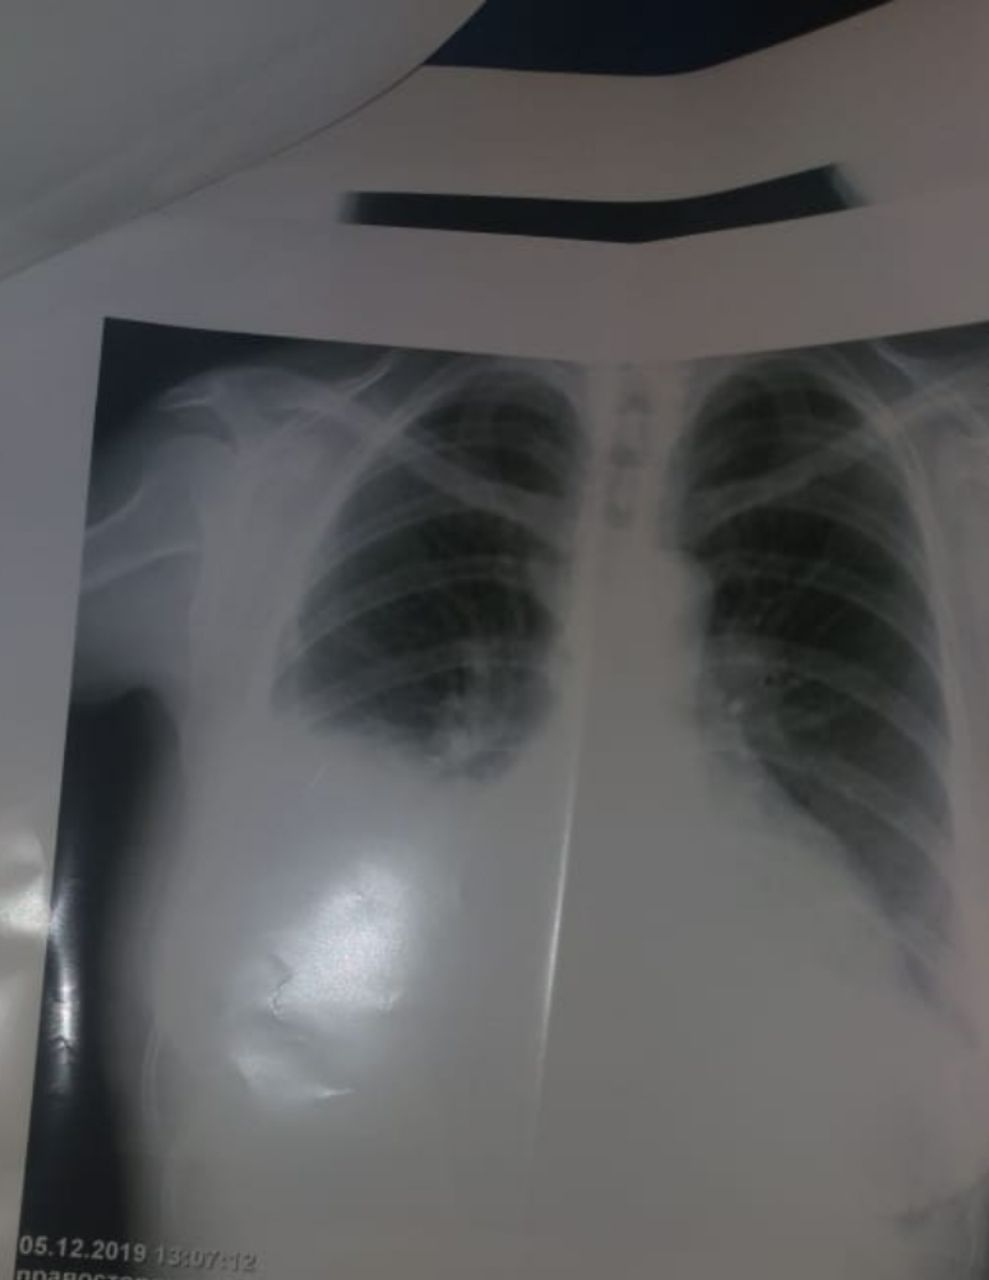

Это от 05.12